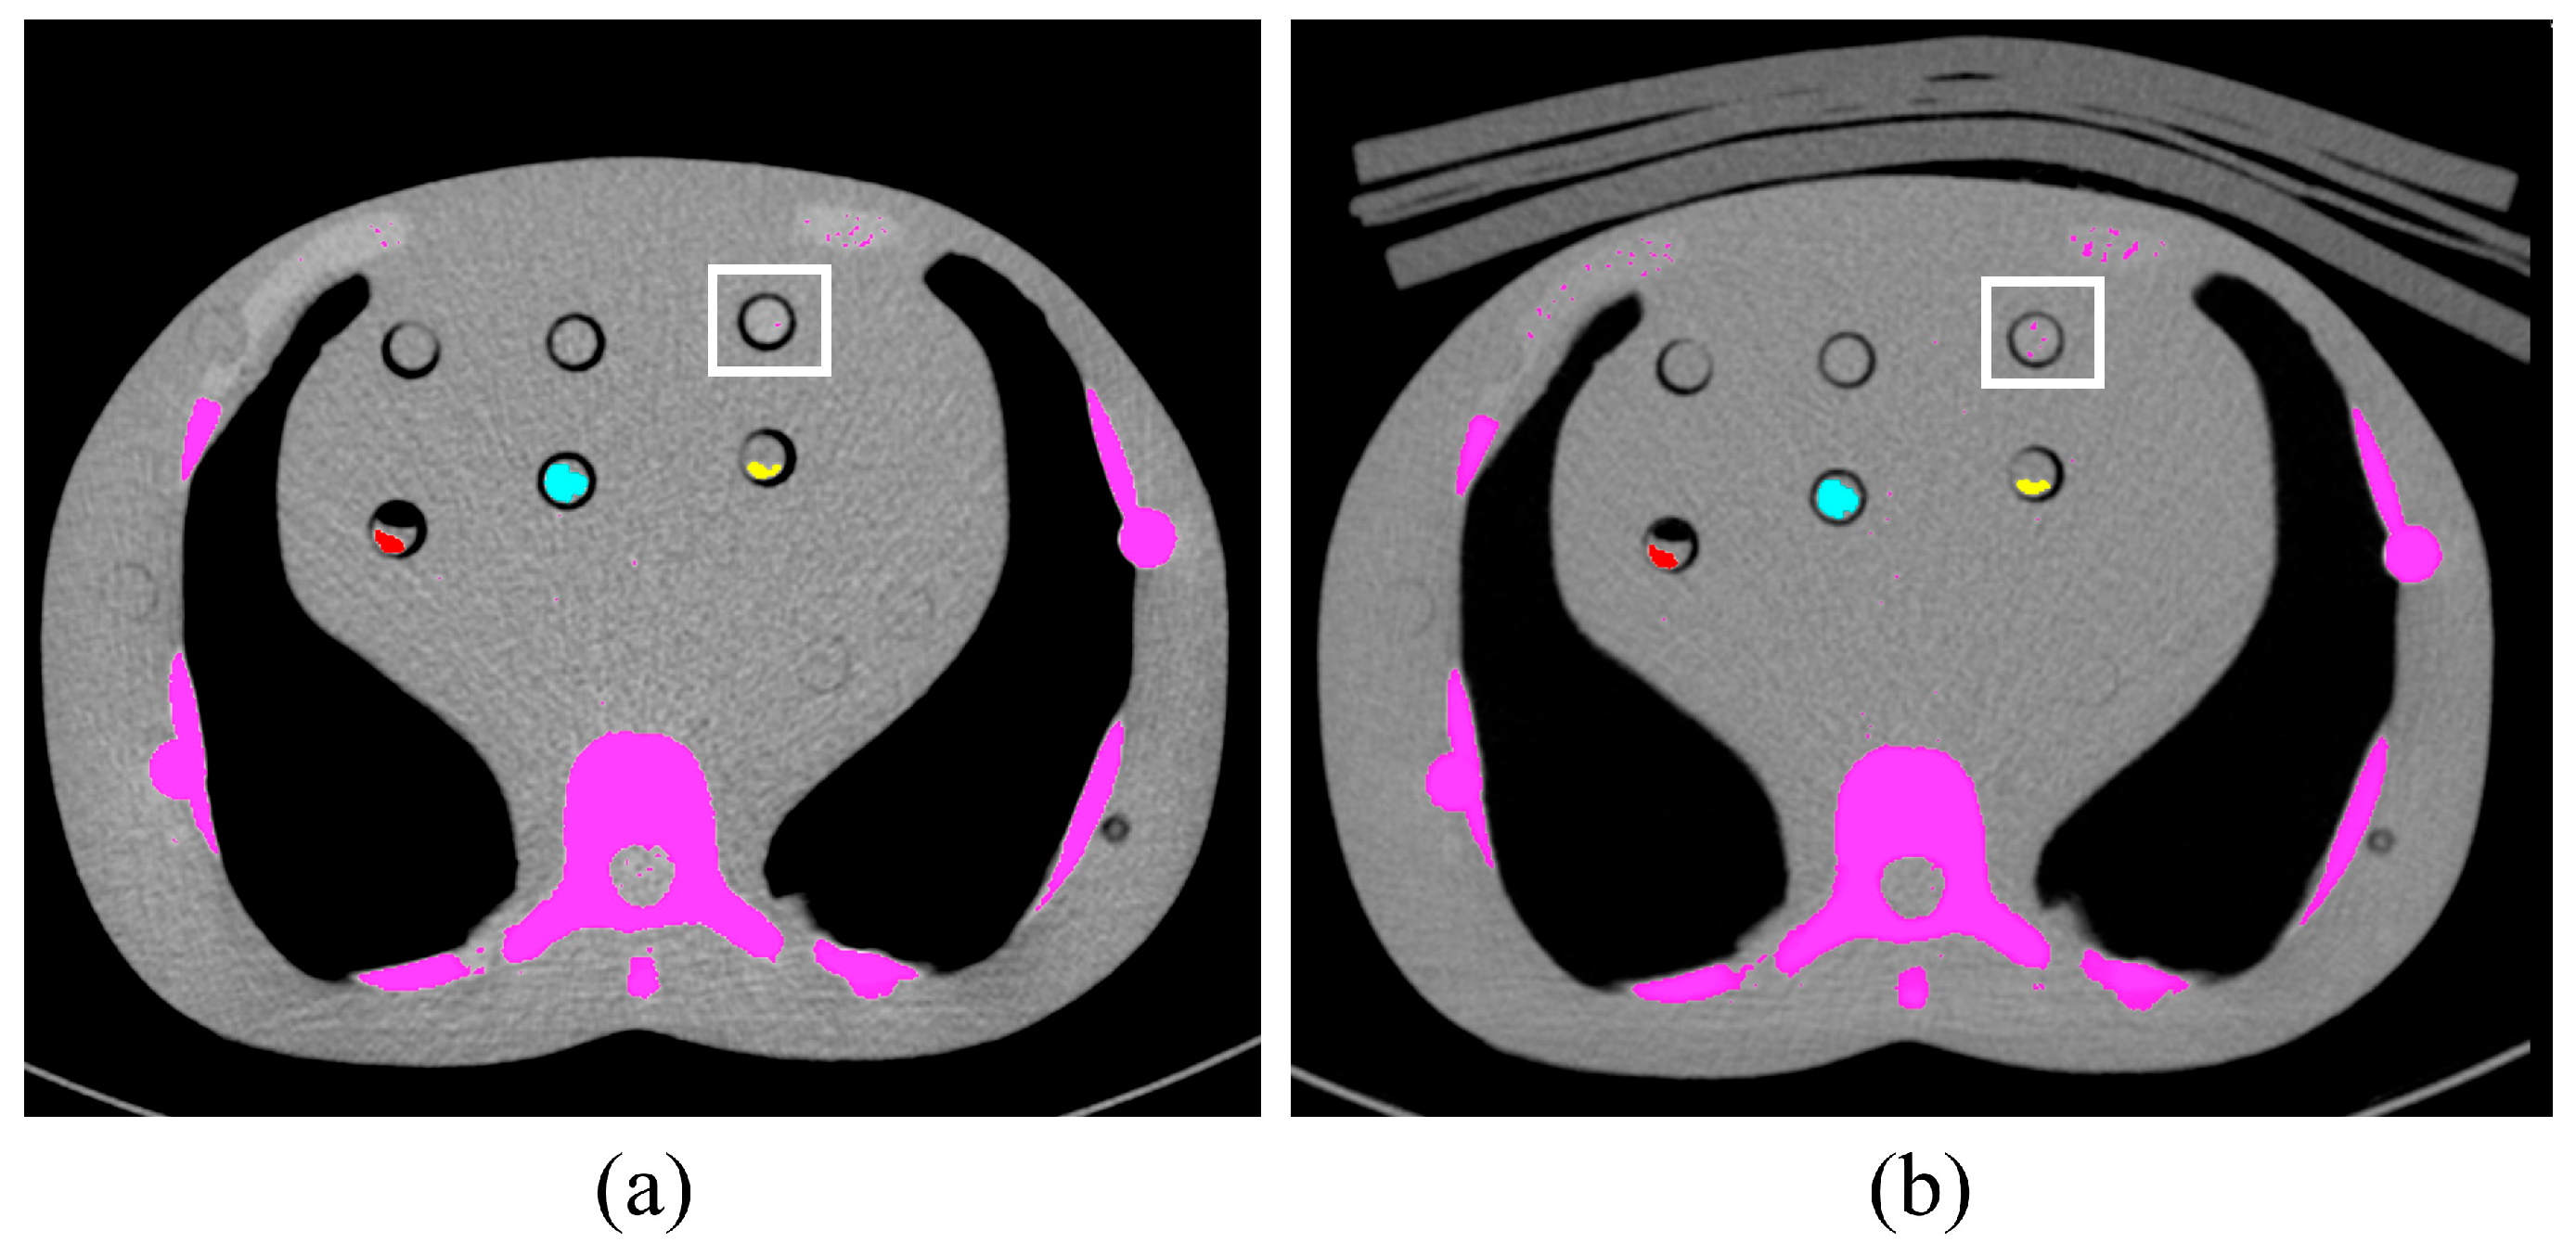

2.3. Image Analysis

2.4. Phantom Study

3.2. Phantom Study